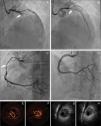

Treatment and in-hospital proceduresOn coronary angiography, severe coronary tortuosity (defined as two consecutive 180-degree turns by visual estimation in a major epicardial artery) was identified in one third of patients (n=8; 29.6%). Diagnosis was enabled by coronary angiography alone for the majority of cases (92.5%; n=25). Intracoronary imaging (optical coherence tomography [OCT]/intravascular ultrasound [IVUS]) was only performed in two patients (Figure 1). In general, only one artery was identified with SCAD, apart from one case, where dissection was found in multiple territories (diagonal, obtuse marginal and right coronary arteries [RCA]). The territory of the LAD was the most commonly involved (n=13), followed by the circumflex artery (n=10) and RCA (n=5). Only one patient had dissection of the left main coronary artery (LMCA). The most common angiographic pattern was type 2 dissection (n=17; 63%), followed by type 1 (n=10; 37%), and 48.1% (n=13) of patients had initial thrombolysis in myocardial infarction (TIMI) flow 0-1.

Panel A: Coronary angiography from patient 8 – spontaneous coronary artery dissection (SCAD) type 1, extending from left main coronary artery to left anterior descending artery (LAD). Panel B: Coronary angiography from patient 8 showing the result obtained after guidewire advancement to the true LAD lumen. Panel C: Coronary angiography from patient 11 showing diffuse lumen narrowing involving the proximal and mid segments of right coronary artery – SCAD type 2. Panel D: Coronary angiography from patient 11 showing the angiographic result after stent implantation. Panels E-F: Optical coherence tomography from patient 22 of distal segment of right coronary artery, depicting intramural hematoma (asterisk). Panels G-H: Cross-sectional intravenous ultrasound views from patient 9 depicting intramural hematoma (asterisk) causing luminal stenosis in the mid-LAD.

Complementary techniques such as IVUS and OCT contribute to better identification and classification of SCAD. IVUS has a lower spatial resolution (150-200 μm), but has deeper penetration, allowing full vessel wall visualization. It can determinate the true and false lumen and detect intramural hematoma (IMH) in its full extension.13 Although the poorer penetration of OCT hampers visualization of the full extent of IMHs, it is more sensitive, has much higher resolution (10-20 μm) and can visualize intimal tears, and true and false lumens. It is also superior in visualizing strut apposition, allowing stent optimization if angioplasty is performed.4,14-16 We only used these tools to confirm diagnosis or to guide SCAD treatment in two procedures, as we only recently acquired the equipment.